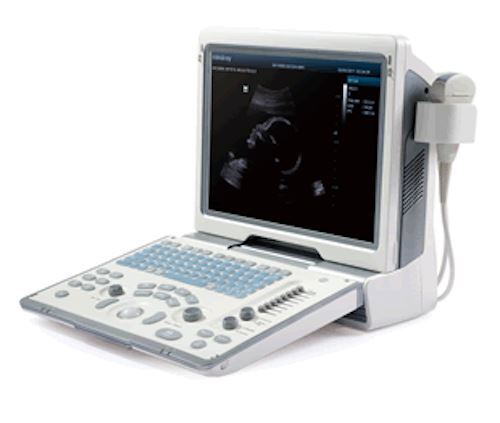

MindRay Diagnostic Ultrasound System DC7

Sale price$ 39,487.99

Save $ 700.00